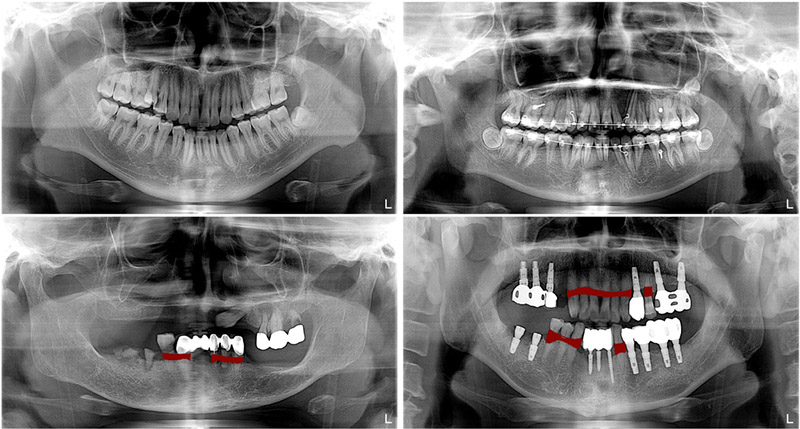

📸 تشخیص و تصویربرداری تخصصی تحلیل استخوان (نقش رادیوگرافی و CBCT)

تشخیص دقیق میزان و الگوی تحلیل استخوان نیازمند تصویربرداری تخصصی است:

• رادیوگرافی پری‌آپیکال (تک دندان): استاندارد طلایی برای ارزیابی تحلیل‌های موضعی استخوان اطراف نوک ریشه.

• عکس پانورامیک: برای مشاهده کلی فک‌ها و ارزیابی عمومی ارتفاع و تراکم استخوان.

• توموگرافی کامپیوتری با پرتو مخروطی (CBCT): این پیشرفته‌ترین ابزار تصویربرداری یک تصویر سه‌بعدی از استخوان‌ها ارائه می‌دهد. دکتر صفورا امامی از CBCT برای تعیین دقیق حجم استخوان باقی‌مانده و تشخیص تحلیل‌های بسیار خفیف یا پنهان استفاده می‌کند.

بیمار در مراحل اولیه معمولاً دردی حس نمی‌کند. تنها راه تشخیص، معاینه توسط دندانپزشک و بررسی عکس‌های رادیوگرافی به‌ویژه رادیوگرافی پانورامیک (OPG) یا سی‌تی‌اسکن دندانی (CBCT) است. این تصاویر میزان کاهش ارتفاع و تراکم استخوان اطراف ریشه دندان را مشخص می‌کنند.